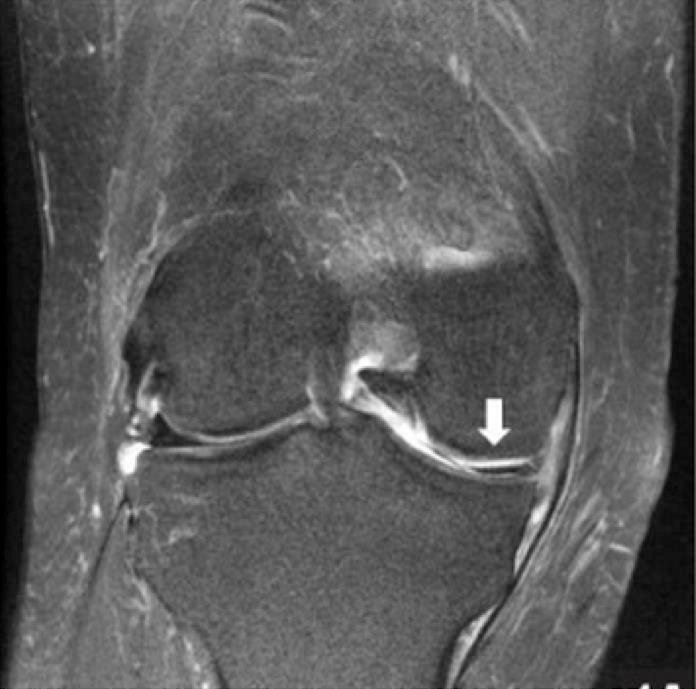

MRI

If we are unsure of your diagnosis or we would like to understand more about the extent and type of the meniscal tear, then we may refer you for an MRI scan. MRI scans are also very useful to assess for any other contributing factors such as an associated ligament tear. We can refer you directly without going to your GP.